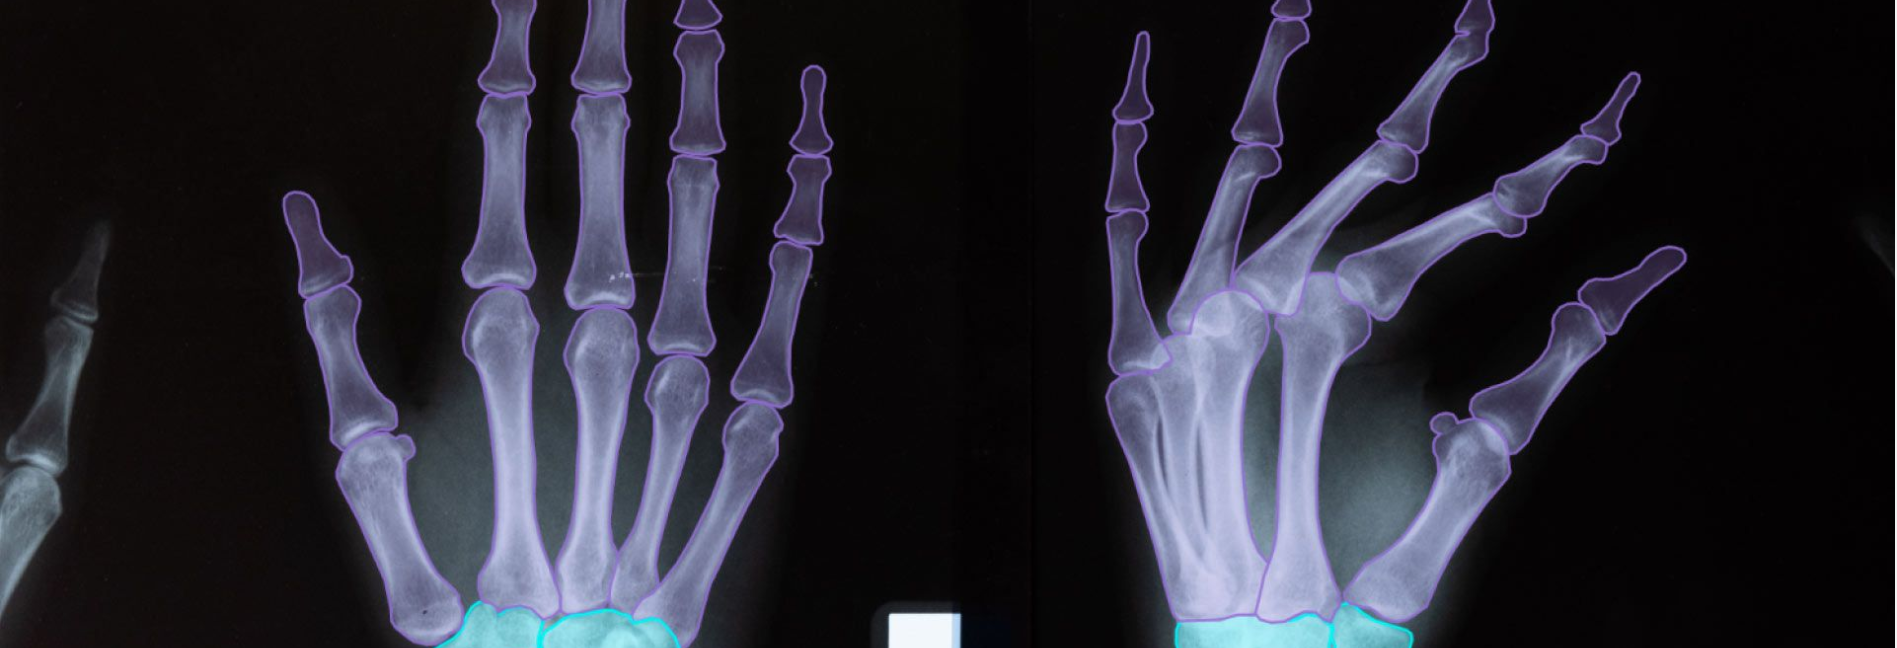

Одне із застосувань штучного інтелекту – радіологія. Ця технологія може аналізувати складні медичні зображення, як-от рентгенівські промені, КТ та МРТ, швидше, ніж експерт-людина. Це дозволяє лікарям швидше визначати потенційні ризики для здоров’я та покращує їхню здатність планувати відповідне лікування для своїх пацієнтів.

ШІ в медичній візуалізації та аналізі

Одним із найбільш перспективних застосувань штучного інтелекту (ШІ) в охороні здоров’я є медична візуалізація та аналіз. Завдяки комп’ютеризованим алгоритмам штучний інтелект може розбивати складні дані зображень і аналізувати їх для цілого ряду діагностичних цілей. Це має численні переваги як для пацієнтів, так і для медичних працівників, включаючи швидшу діагностику, більш точні показники та покращення результатів лікування.

Домінування програмного забезпечення в рамках штучного інтелекту на ринку охорони здоров’я також відображається в його використанні для медичної візуалізації. Комп’ютери на базі штучного інтелекту можуть швидко обробляти великі обсяги даних, виявляючи тонкі закономірності або зміни, які людське око може не помітити. Наприклад, штучний інтелект може визначати потовщення в конкретних м’язових структурах або відстежувати зміни кровотоку, які можуть вказувати на певні захворювання. Крім того, він виявився корисним для виявлення ракових уражень, а також моніторингу неврологічних захворювань і торакальних ускладнень.